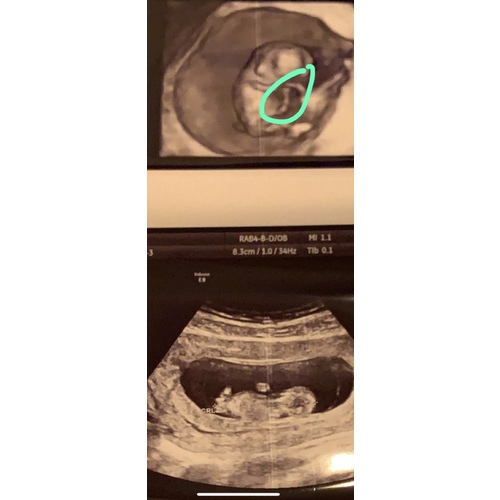

Wat een mooie echo's! Ik zou me er geen zorgen over maken hoor er is altijd vanalles te zien vooral bij een 3d/4d echo. Zolang de verloskundige niets heeft gezegt zou ze niets geks hebben gezien.

Dank je wel voor je reactie. Heb echt geen oogje dicht gedaan deze nacht. Gepiekerd, gepiekerd… op de app zwangerschap+ heeft de baby bij week 9 nog zo’n staartje… daarmee dat ik me zorgen maak! 😢

You made my day. Dank je. Ik was echt zo ongerust. De vroedvrouw zei dat alles ok was hoor maar toen ik thuis kwam en wou genieten dacht ik “oh nee weer iets om te piekeren!”. Wat is dat nub? 😀😅 en de navelstreng is toch wat ik hier op de echo heb aangeduid? Ik ben vandaag trouwens 10+5. Dus gisteren +4. Maar volgens de vroedvrouw was ik gisteren 10+6. Ze zei dat het kan schommelen. De afgelopen 2 sessies klopten toen wel qua weken en dagen. Is dit normaal? 😀